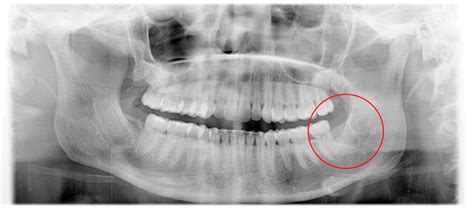

Few dental experiences are as intimidating or painful as dealing with a severe dental abscess. When a tooth is compromised by deep decay, trauma, or gum disease, bacteria can enter the pulp chamber, leading to a serious infection. In many cases, dentists aim to save the natural tooth; however, there are scenarios where an infected tooth extraction becomes the only viable solution to prevent the infection from spreading to the jawbone, bloodstream, or other parts of the body. Understanding the process, the risks, and the recovery period is essential for anyone facing this common yet significant dental procedure.

An infected tooth extraction is typically recommended when a tooth is so severely damaged by decay or infection that it cannot be restored. While procedures like root canal therapy are often the first line of defense, they are not always successful or applicable depending on the extent of the infection. When the infection reaches a critical stage, leaving the tooth in the mouth poses a severe risk to your systemic health.

• Advanced Periodontal Disease: When the infection has destroyed too much of the bone supporting the tooth, making it loose and untreatable.

• infected tooth extraction site pictures